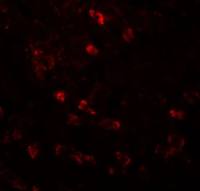

IHC-P analysis of lung tissue sections from LPS exposed mouse using GTX53099 VEGFB antibody [6E72].

Left : Primary antibody

Right : Negative control